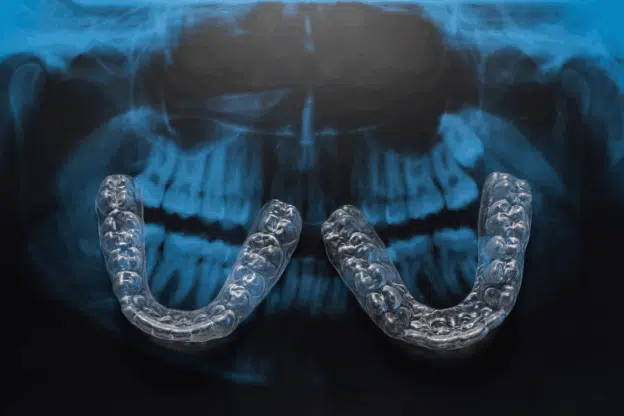

For adults, treatment options include Ceramic braces, metal braces, Invisalign, self-ligating ceramic braces, and accelerated orthodontic solutions tailored to adult patients. These solutions straighten teeth, optimize jaw alignment, support airway efficiency, and relieve muscle tension. Many adults report better sleep, reduced jaw strain, and improved posture after treatment.

Even in adulthood, bone can remodel under gentle orthodontic forces. Treatments like self ligating ceramic braces or Invisalign for adults allow teeth to shift gradually, widening arches and supporting natural tongue positioning, which improves airflow and airway stability.